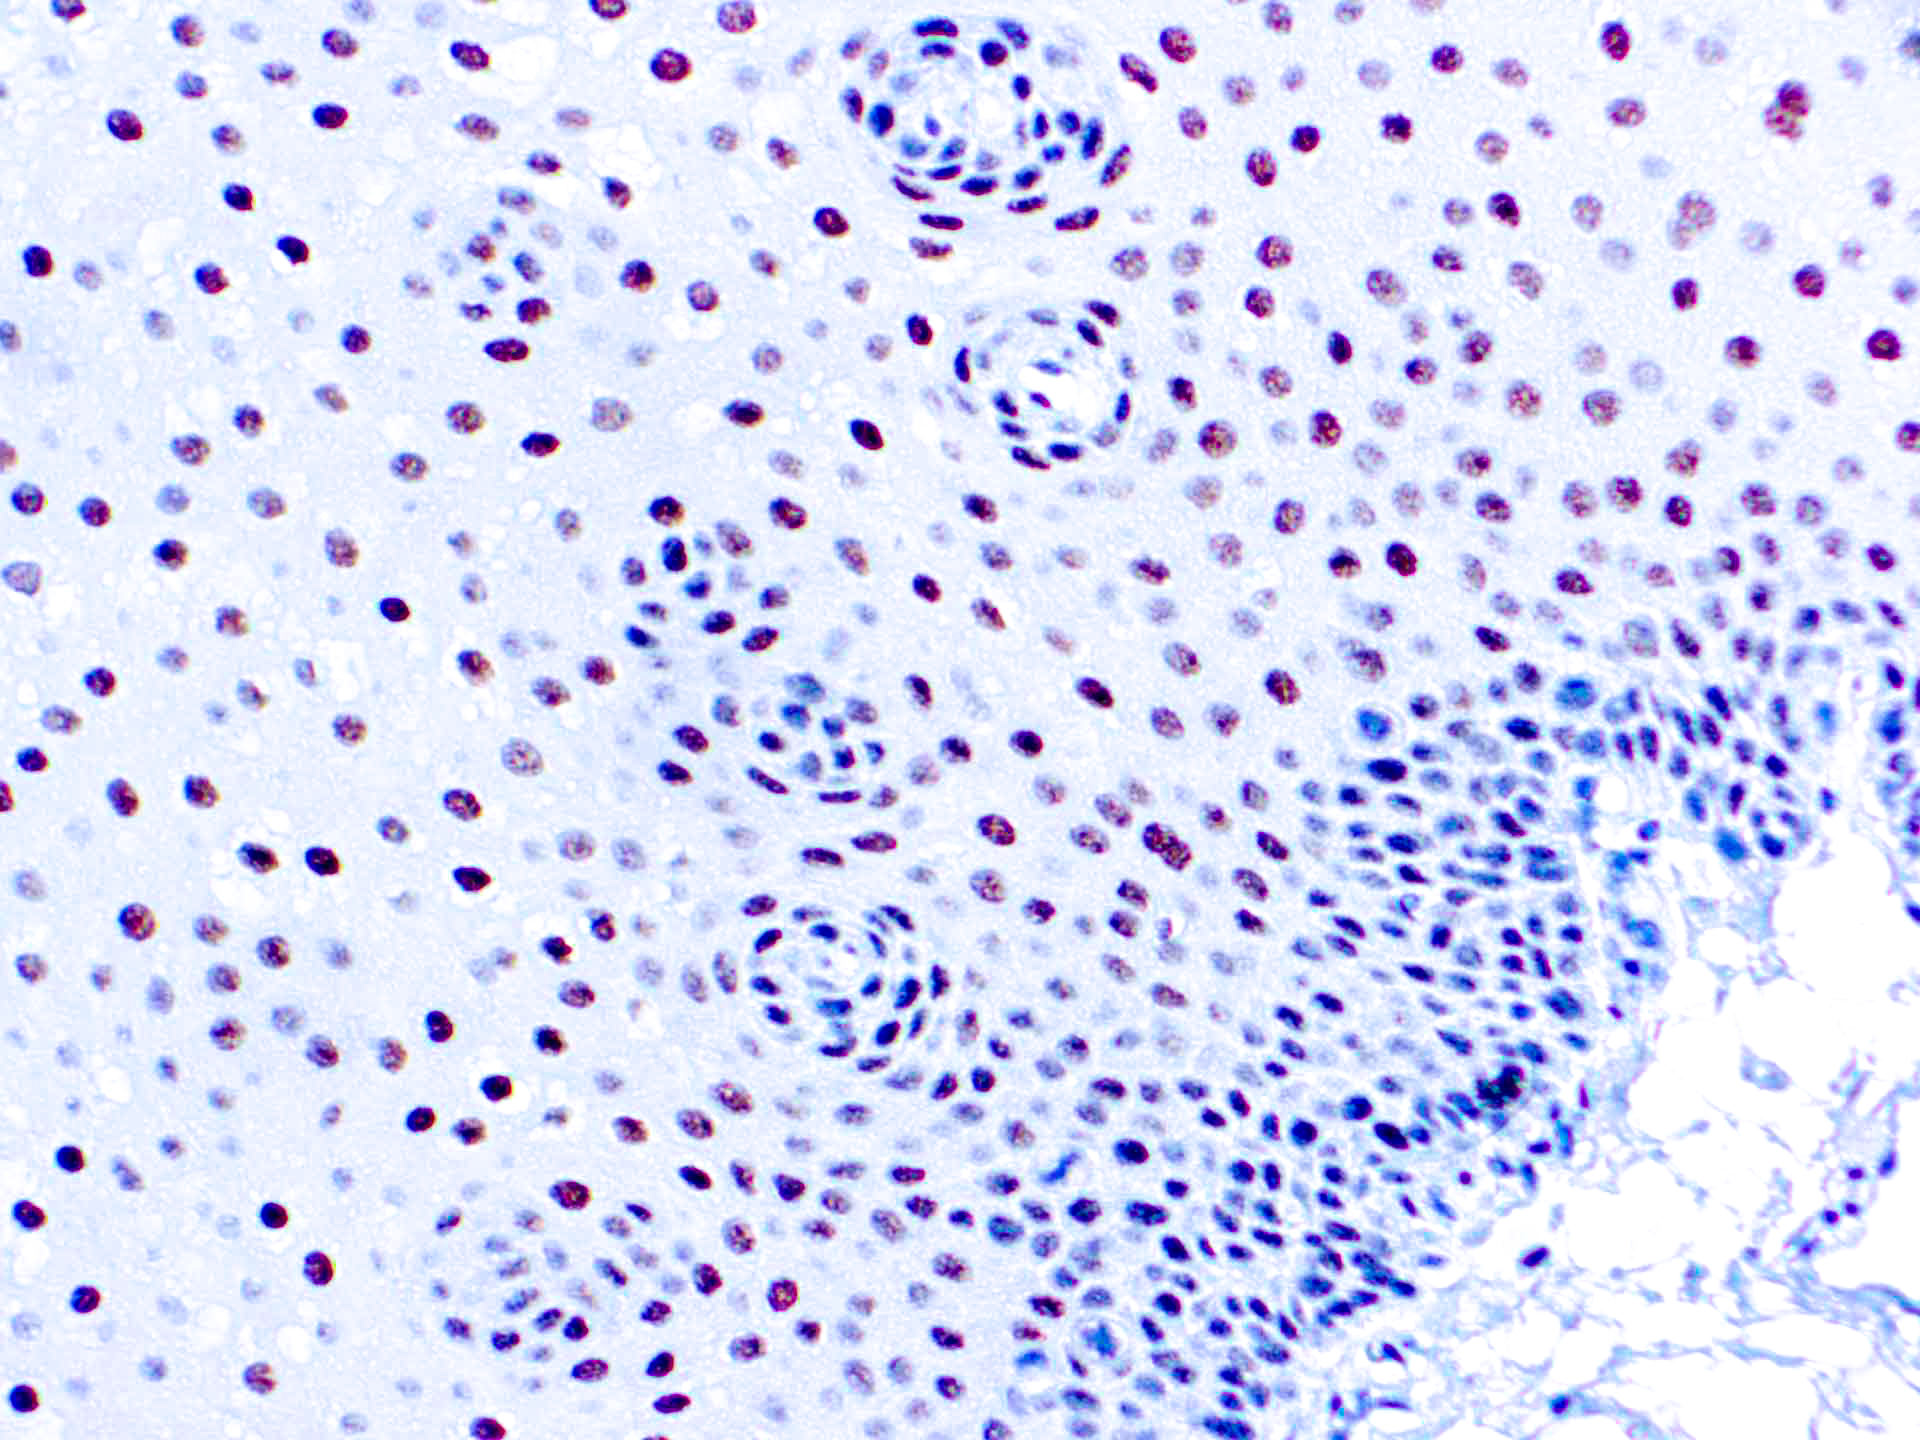

ERCC1

This antibody reacts with a 33-36 kDa protein known as ERCC1 (excision repair cross complementing) polypeptide. ERCC1 is required for nucleotide excision repair of damaged DNA and is homologous to RAD10. In mammalian cells, XPG cleaves 3’ of the DNA lesion while ERCC1-XPF complex makes the 5’ incision.

| Cellular Localization | Nuclear |

| Positive Control Tissue | Tonsil |